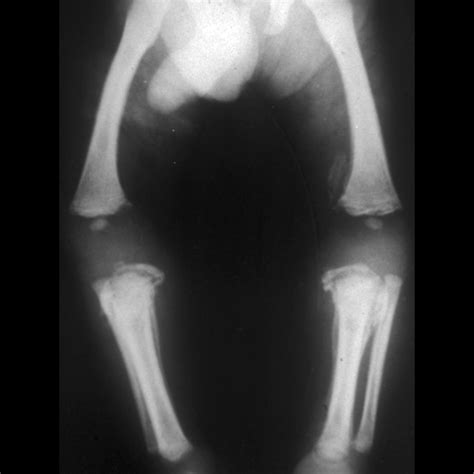

Orthopedic injuries can range from minor sprains to severe fractures, each requiring specific medical attention. Among these, a Bucket Handle Fracture is a unique and critical type of injury that demands immediate and precise treatment. This type of fracture involves a segment of bone that is displaced, often resembling a bucket handle, hence the name. Understanding the causes, symptoms, diagnosis, and treatment options for a Bucket Handle Fracture is essential for both medical professionals and patients.

A Bucket Handle Fracture is a specific type of fracture where a segment of bone is displaced, often in a manner that resembles the handle of a bucket. This type of fracture is commonly seen in the knee, particularly in the medial meniscus, but can also occur in other joints. The fracture typically involves a longitudinal split in the bone, with the displaced segment often remaining attached to the surrounding ligaments or tendons.

• Imaging Tests: X-rays, MRI, or CT scans to visualize the fracture and determine the extent of the damage.

Imaging tests are crucial for confirming the diagnosis and planning the appropriate treatment. X-rays can show the fracture line, while MRI and CT scans provide detailed images of the soft tissues and bone structure.